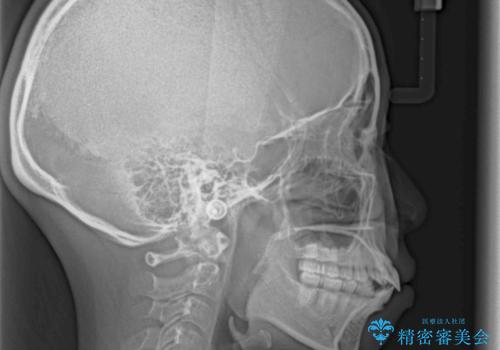

上下前歯が著しく前突している状態であったので、上下左右の第1小臼歯4本を抜歯し、ワイヤー装置にて矯正治療を行うこととしました。

舌の突出癖により、前突になったと考えられたため、舌のトレーニングをしっかりと行うよう指導しました。

4本の歯を抜歯したことで、飛び出していた口元が引っ込み、横顔が大きく改善されました。